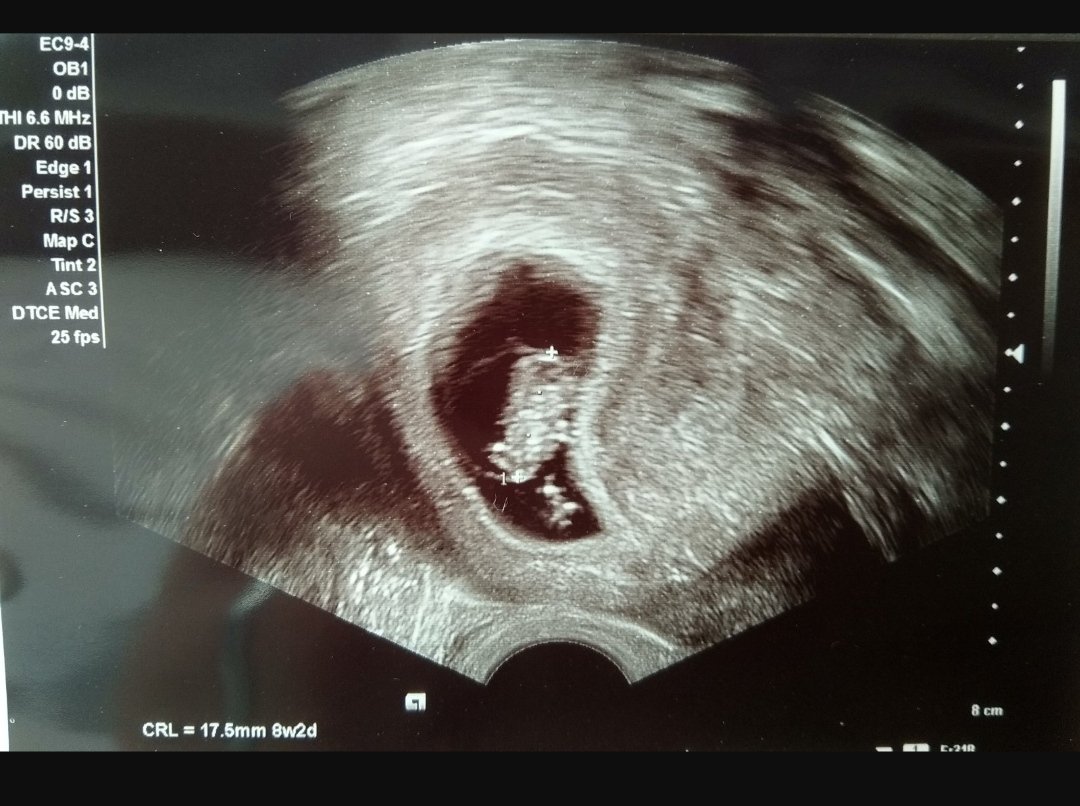

Prvni fotka 7+1 a druha 9+4 😊😊